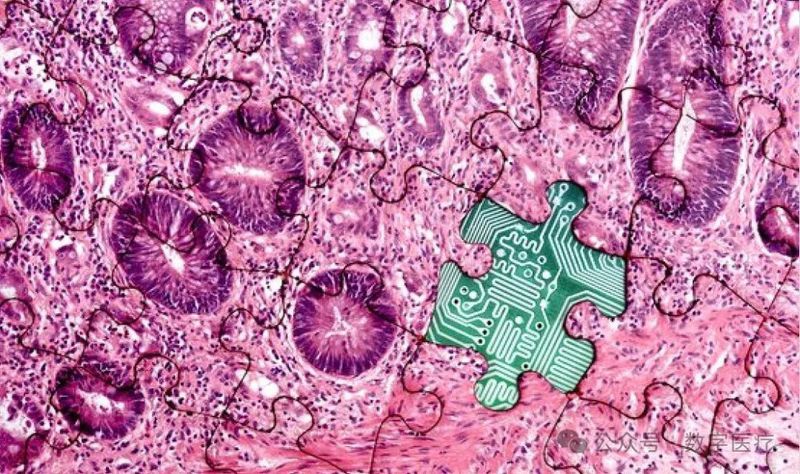

本文介绍了“探路者”,一个用于医学诊断决策的多模态多智能体系统,并将其应用于组织病理学分析。该系统旨在模拟病理科医生在诊断过程中进行多尺度、迭代式决策的过程,通过整合多个AI智能体来实现对全切片图像的精准、可解释的诊断。“探路者”的创新之处在于其多智能体协作框架,以及将自然语言处理与计算机视觉相结合的能力,从而在提高诊断准确性的同时,增强了诊断结果的可解释性。